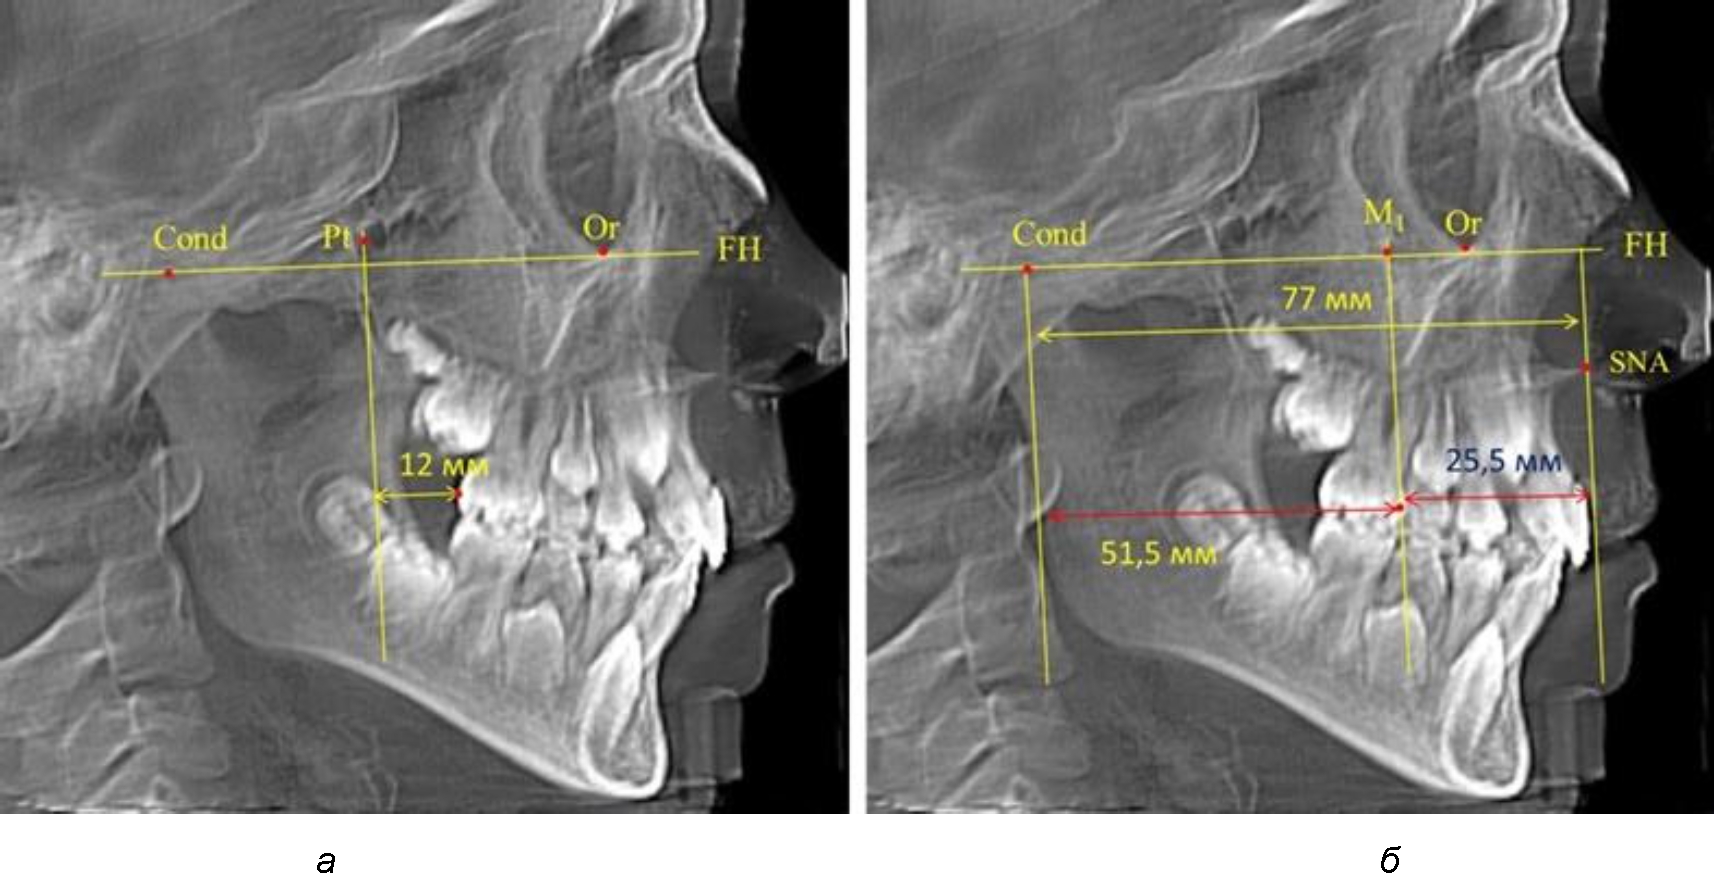

Рис. 2. Особенности положения первых моляров по R. E. McDonald (а) и по предложенному методу (б) при уменьшенном молярно-крыловидном расстоянии

Рис. 3. Особенности положения первых моляров по R. E. McDonald (а) и по предложенному методу (б) при увеличенном молярно-крыловидном расстоянии

Так, при расстоянии от крыловидной вертикальной плоскости PTV до дистальной поверхности верхнего первого постоянного моляра в 13 мм сагиттальный размер гнатического отдела был 82 мм. При этом отношение кондилярно-спинального расстояния к кондилярно-молярному размеру (54,5) было близким к коэффициенту 1,5, что представлено на рис. 2.

В то же время при увеличенном расстоянии от крыловидной вертикальной плоскости PTV до дистальной поверхности верхнего первого постоянного моляра, равное 23 мм, сагиттальный размер гнатического отдела составил 92 мм. При этом отношение кондилярно-спинального расстояния к кондилярно-молярному размеру (30,5), так же, как и при малых размерах, было близким к коэффициенту 1,5, что представлено на рис. 3.